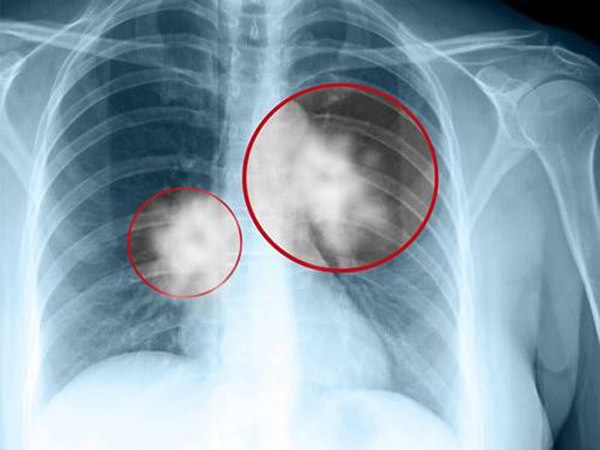

Kết quả xét nghiệm cho thấy người bệnh bị tràn dịch màng phổi hai bên màng tim. Kết quả nhuộm hóa mô miễn dịch dịch màng tim có dấu hiệu ung thư biểu mô tuyến của phổi di căn dịch màng tim, màng phổi.

Theo các bác sĩ, ung thư phổi được chia làm hai loại là ung thư phổi tế bào nhỏ và ung thư phổi không tế bào nhỏ.

Ung thư phổi tế bào nhỏ: là loại có tốc độ phát triển của tế bào cũng như tốc độ di căn nhanh vào máu và một số bộ phận khác trong cơ thể. Thông thường, khi được phát hiện, bệnh nhân mắc phải loại ung thư này đều đã bước vào giai đoạn nặng của bệnh.

Ung thư phổi không tế bào nhỏ: có tốc độ phát triển của tế bào và di căn chậm hơn so với ung thư phổi tế bào nhỏ. Vì vậy, nếu được phát hiện sớm và chữa trị kịp thời, bệnh nhân có hi vọng sống cao hơn. Theo thống kê của Bộ Y tế, có tới 80% người mắc ung thư phổi là ung thư không tế bào nhỏ. Trong đó, loại ung thư này chia thành 3 nhóm nhỏ: ung thư phổi tuyến, ung thư phổi biểu mô bào vảy và ung thư phổi biểu mô tế bào lớn.